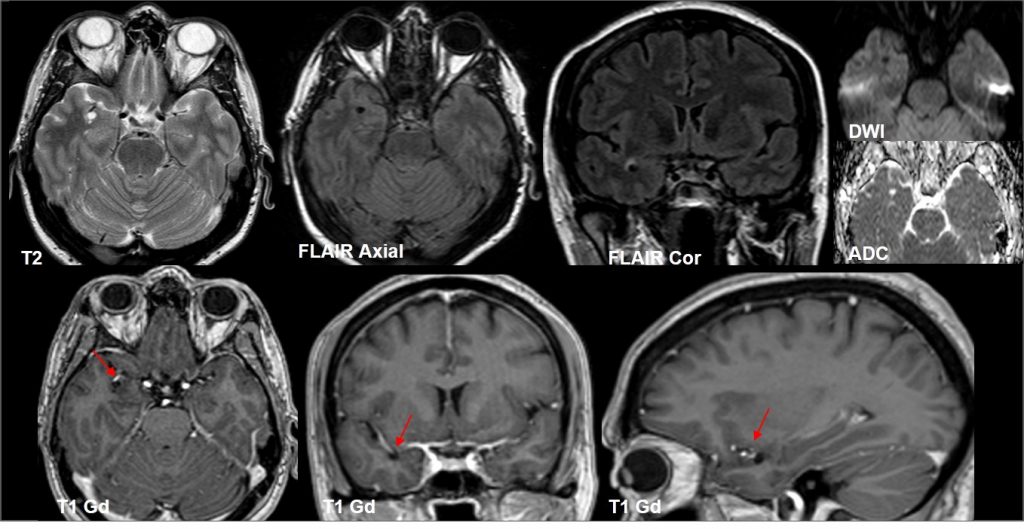

RM cerebral donde se observa lesión de 5 mm en región temporal anterior derecha, próxima a ramas de la ACM derecha (flechas), hiperintensa en T2, hipointensa en T1 y FLAIR, con periferia hiperintensa en FLAIR (punta flecha). Se asocia a pequeño espacio perivascular adyacente (asterisco). No se evidencia realce tras la administración de contraste ni restricción en el estudio de difusión. Control a los 6 y 12 meses, estable.

Espacio perivascular de Virchow Robin temporal anterior dilatado.